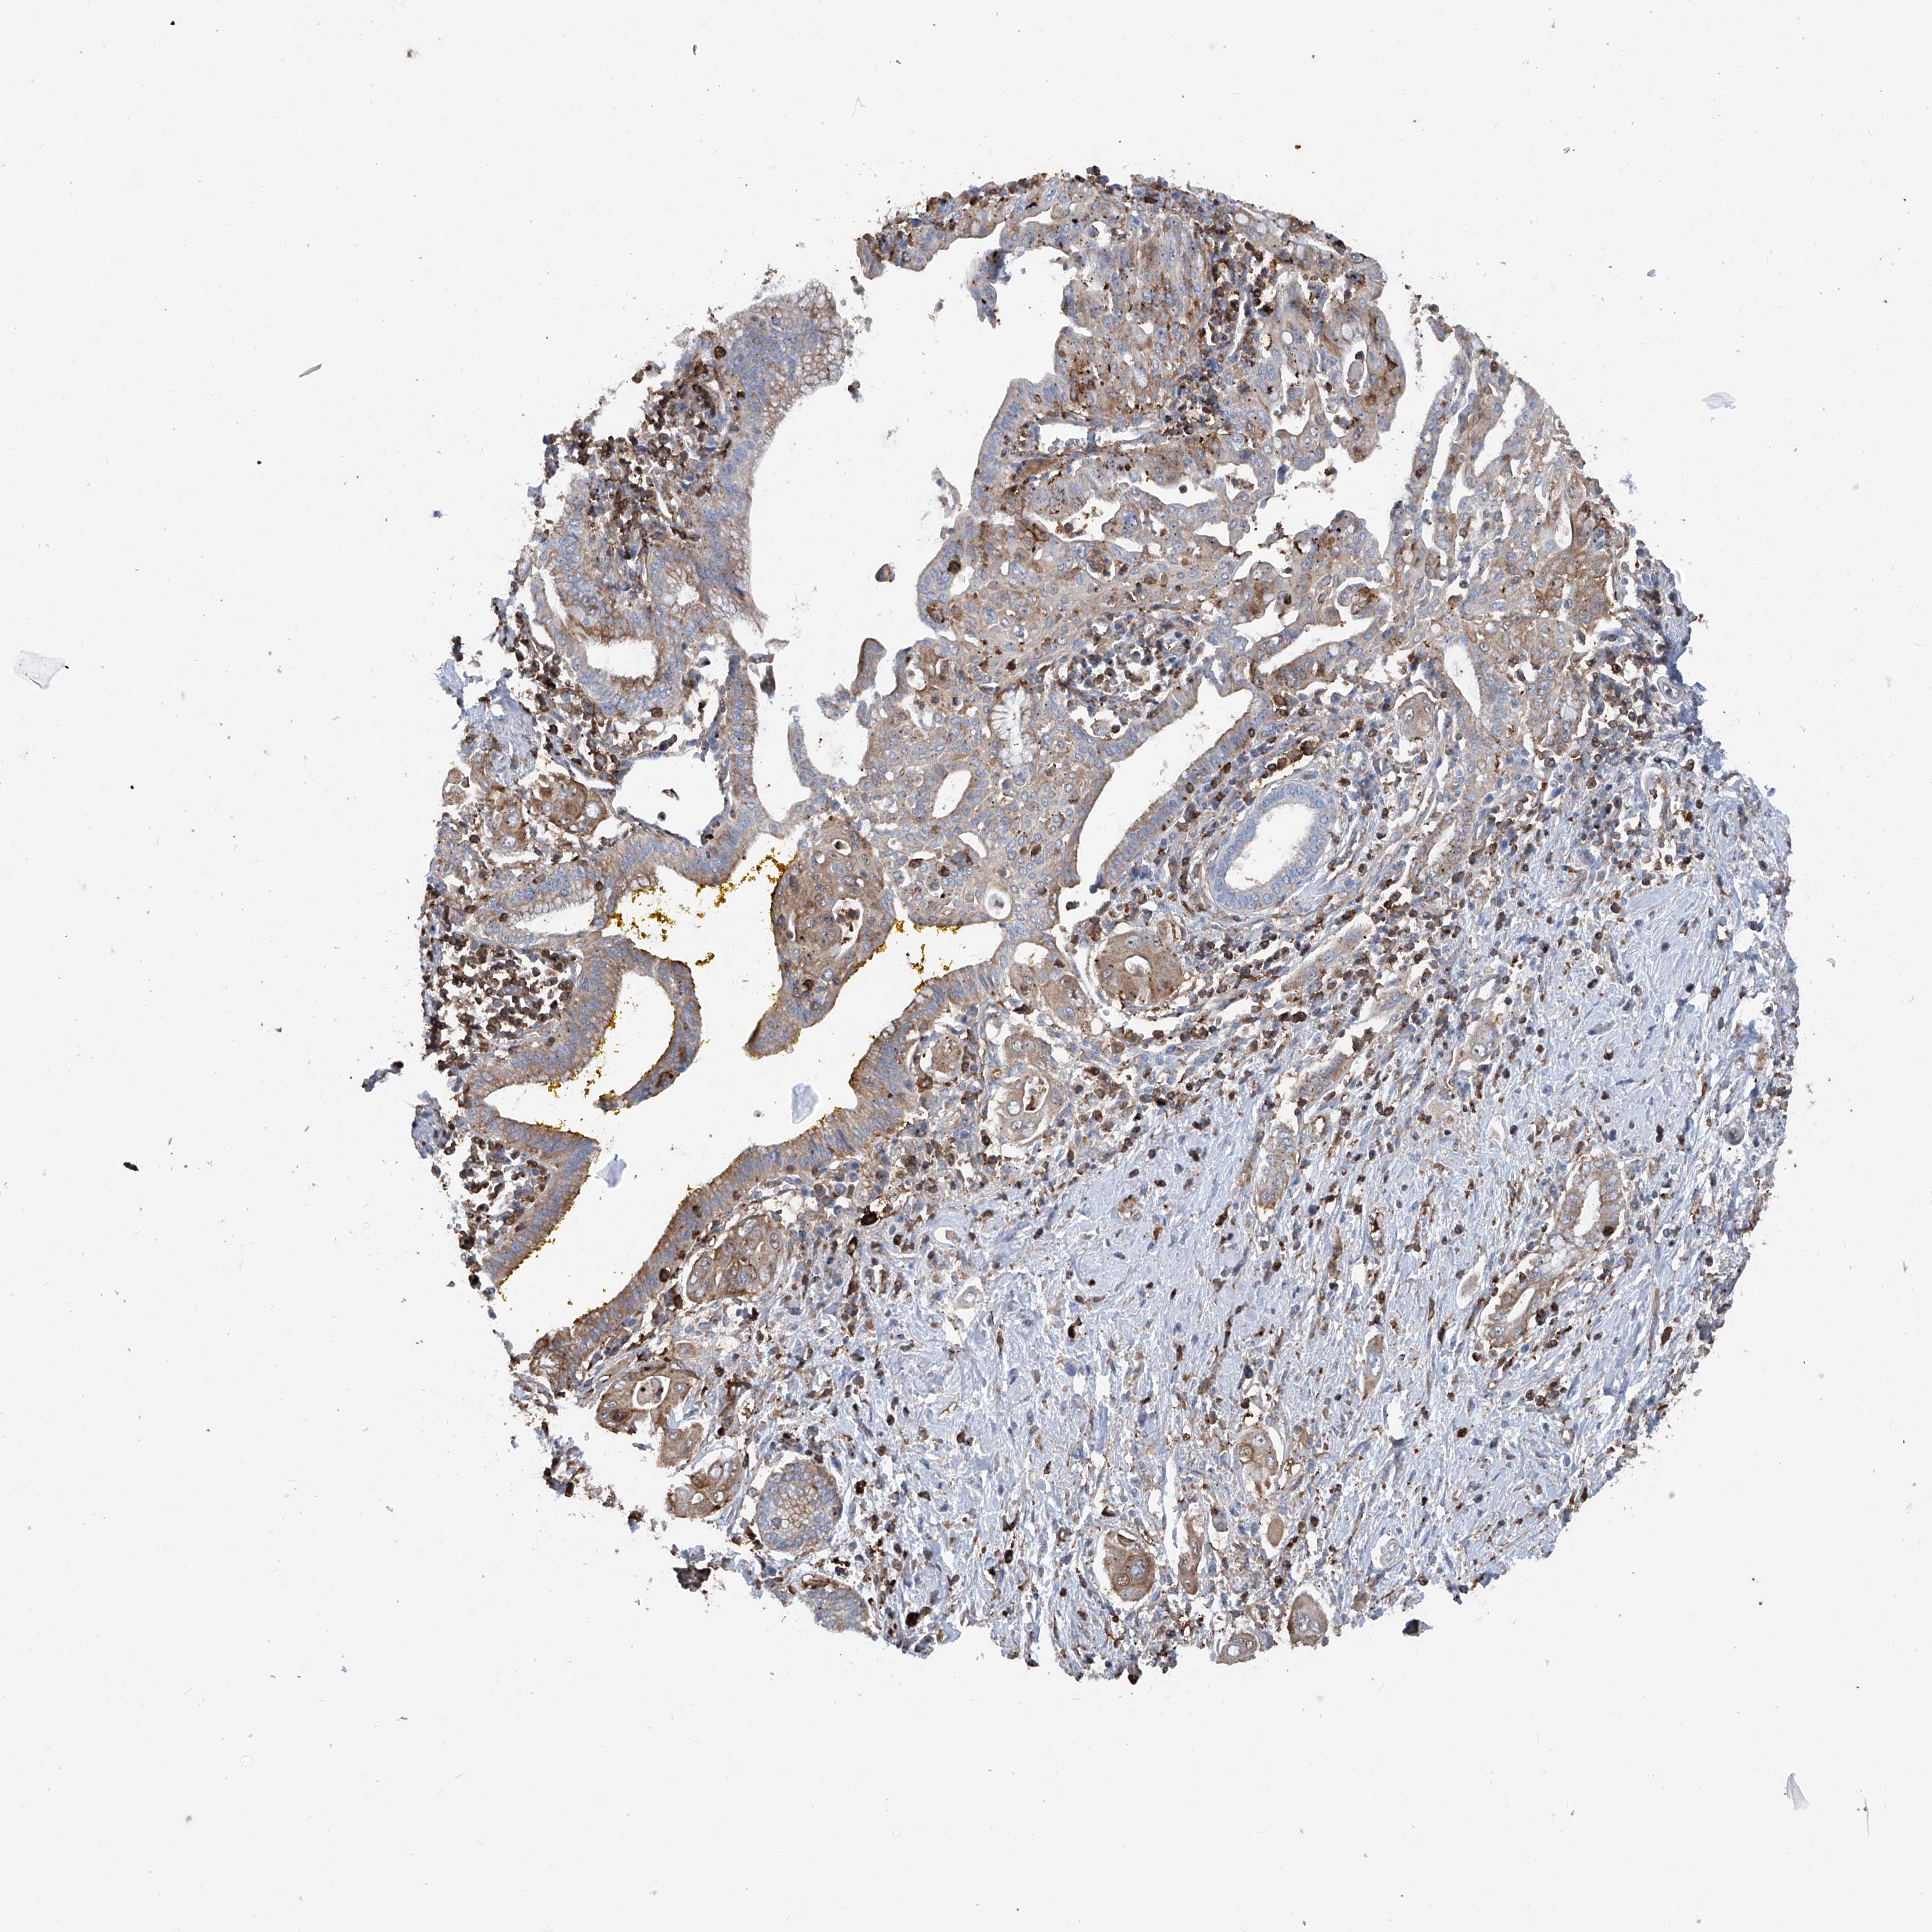

PANCREATIC CANCER - Protein expressioni

A mouse-over function shows sample information and annotation data. Click on an image to view it in a full screen mode. Samples can be filtered based on level of antibody staining by selecting one or several of the following categories: high, medium, low and not detected. The assay and annotation is described here.

Note that samples used for immunohistochemistry by the Human Protein Atlas do not correspond to samples in the TCGA dataset.

Antibody stainingi

Antibody staining in the annotated cell types in the current human tissue is reported as not detected, low, medium, or high, based on conventional immunohistochemistry profiling in selected tissues. This score is based on the combination of the staining intensity and fraction of stained cells.

Each image is clickable and will lead to virtual microscopy that enables deeper exploration of all samples and also displays staining intensity scores, fraction scores and subcellular localization as well as patient and tissue information for each sample.

Antibody HPA028973

Staining

High

Medium

Low

Not detected

Intensity

Strong

Moderate

Weak

Negative

Quantity

>75%

75%-25%

<25%

None

Location

Nuclear

Cytoplasmic/membranous

Cytoplasmic/membranous,nuclear

Adenocarcinoma, NOS